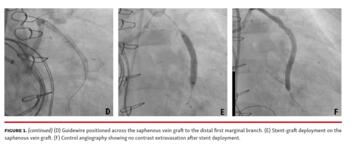

Angiography demonstrated important contrast leakage from the distal body of the saphenous vein graft to the first marginal branch (Figures 1A-1C; Video 1). Remaining grafts were patent. After a cardiac arrest responsive to cardiopulmonary resuscitation during the angiography, we elected to proceed with percutaneous treatment. Using an 8 Fr, JR 4.0 guiding catheter, a 5.0 x 38 mm Atrium Advanta V12 stent-graft (Getinge) was released at the bleeding site. Control angiography showed no contrast extravasation and Thrombolysis in Myocardial Infarction 3 flow (Figures 1D-1F; Video 2). The patient responded with rapid hemodynamic improvement. Subsequently, she developed multiple complications and died 50 days after coronary artery bypass graft surgery.